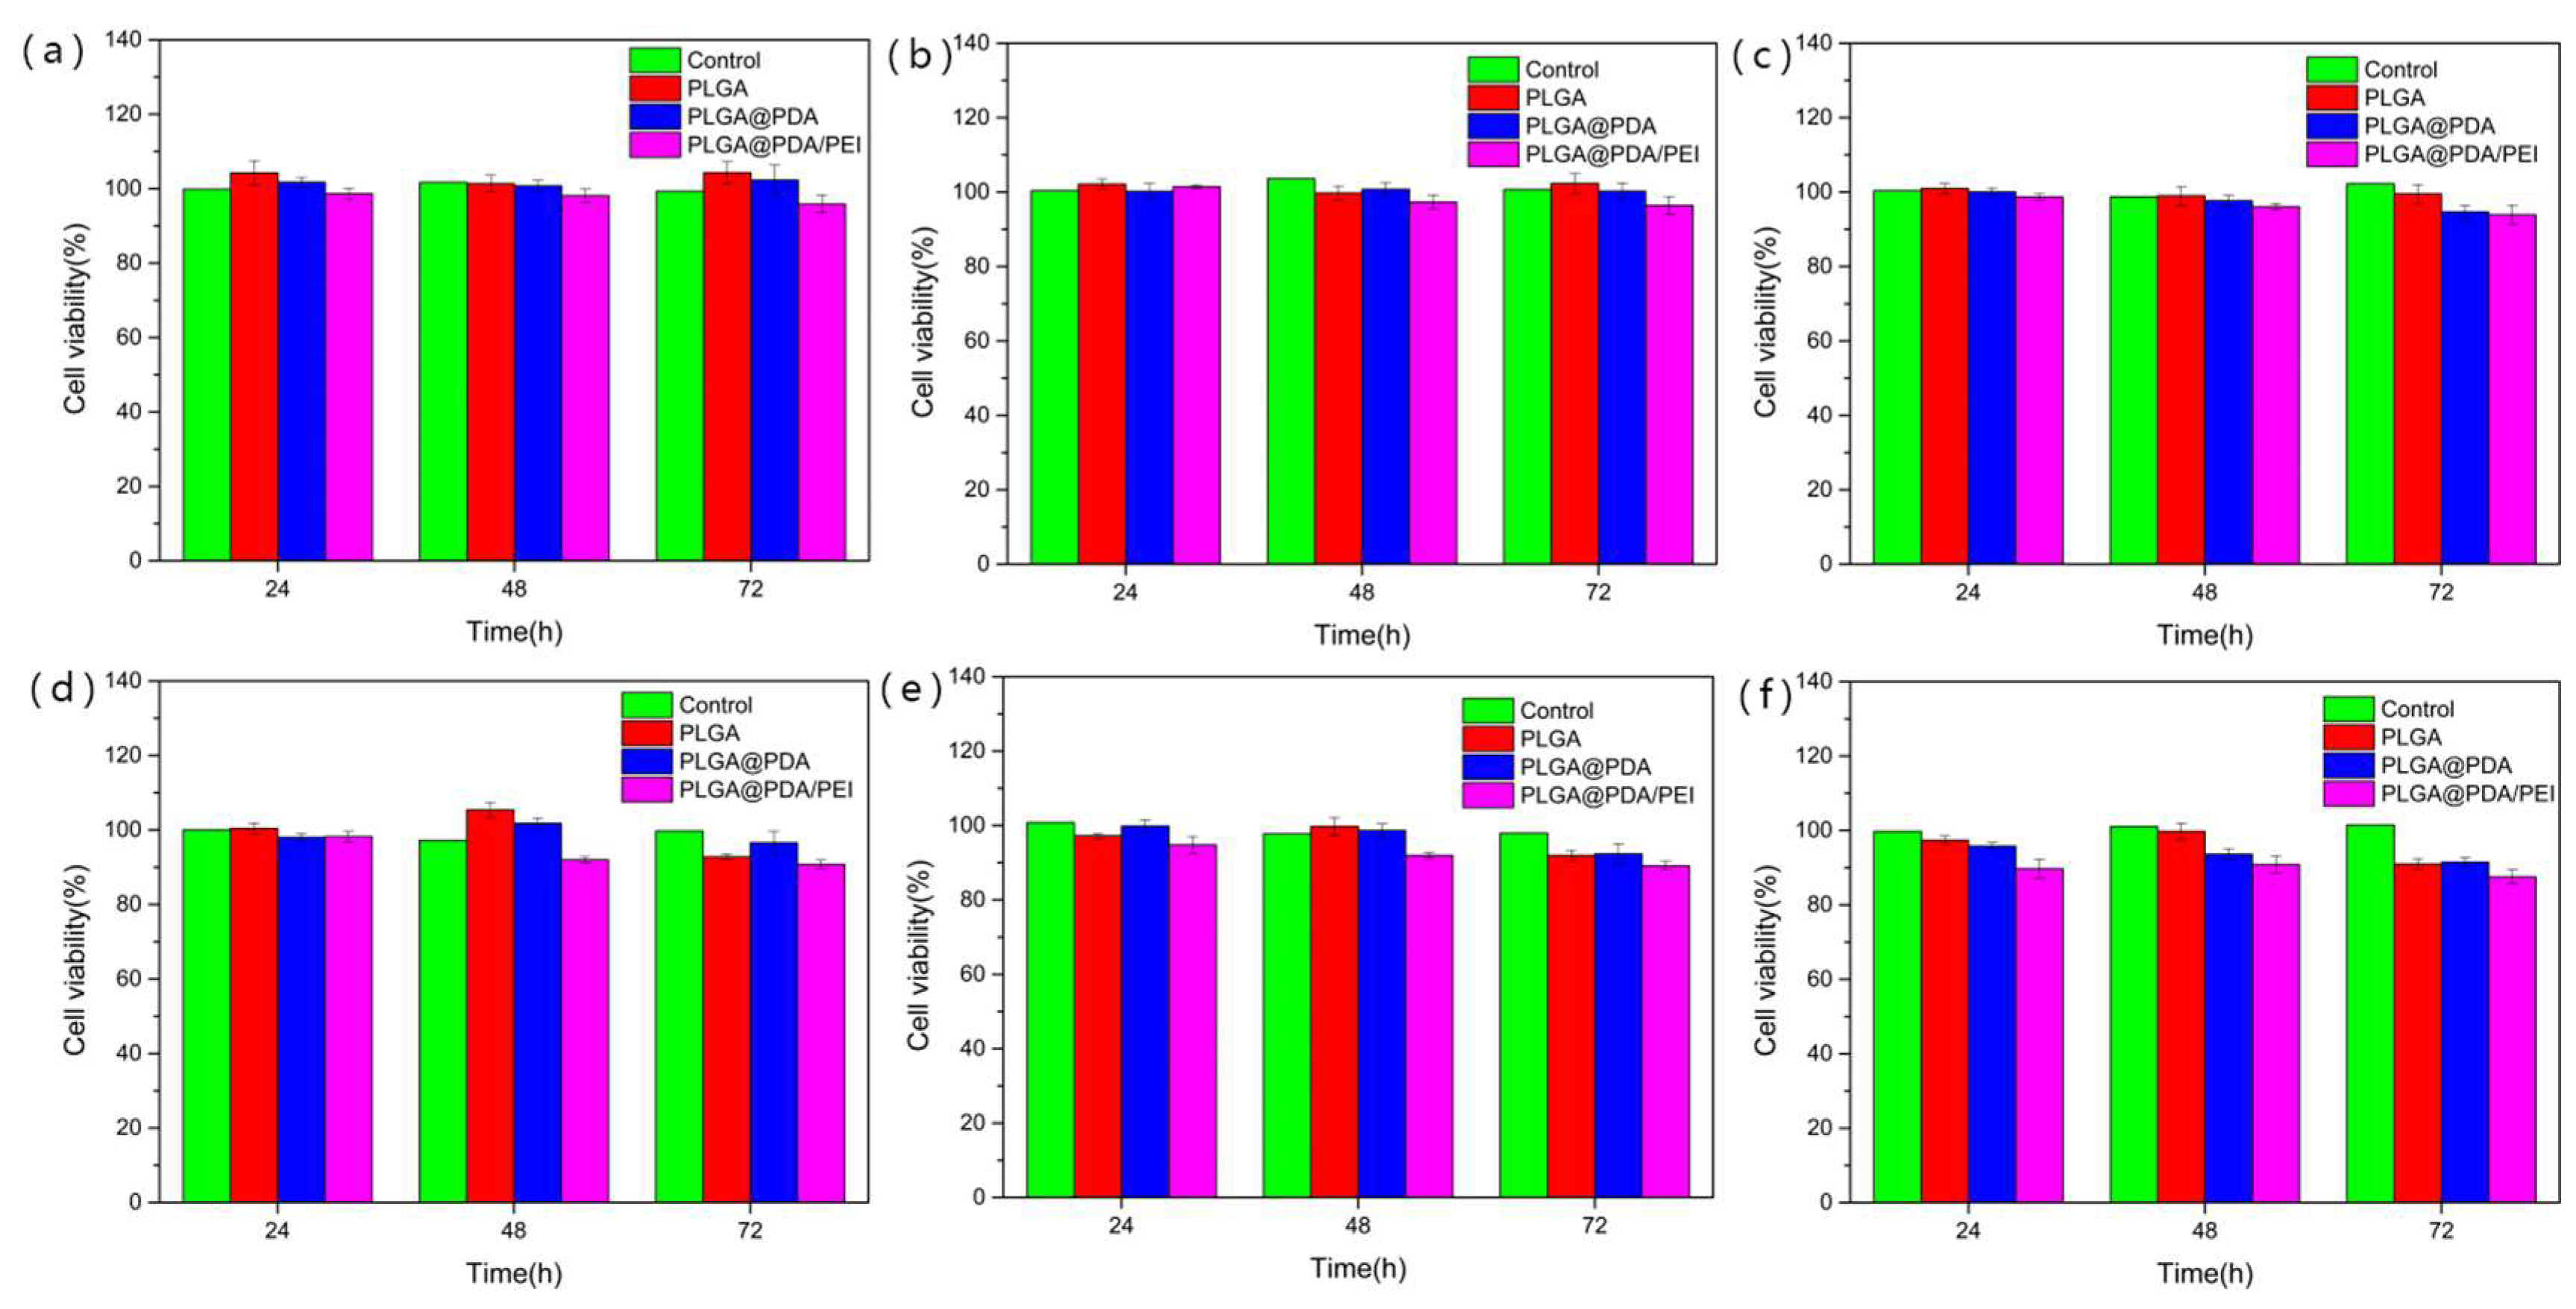

3.6. In-Vitro Cytotoxicity Assessment of Modified PLGA Microspheres